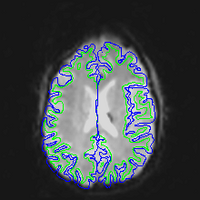

EPI images are significantly distorted relative to true brain anatomy. This is a problem because activation maps created from EPI images are overlaid on T1 images (or cortical surface models created from T1 images) which reflect the true anatomy. The following images show a T1 image with outlines for the outer boundary of gray matter (blue line) and white matter (green line).

Here are uncorrected EPI images with the same boundaries overlaid.

If we stretched the EPI image A qualitative way of judging the effectiveness is to overlay the unwarped EPI on the T1 and see how they match. Here are corrected EPI images with the same boundaries overlaid.